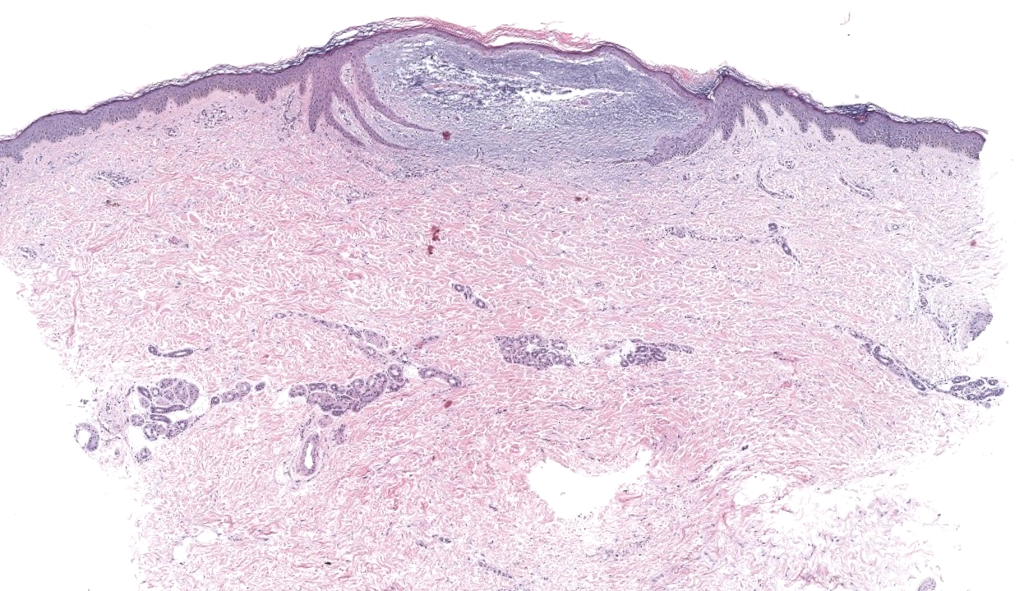

Biopsia adecuada: punch profundo/escisional; pedir Alcian blue pH 2.5, hierro coloidal y hialuronidasa(confirmar hialuronato).